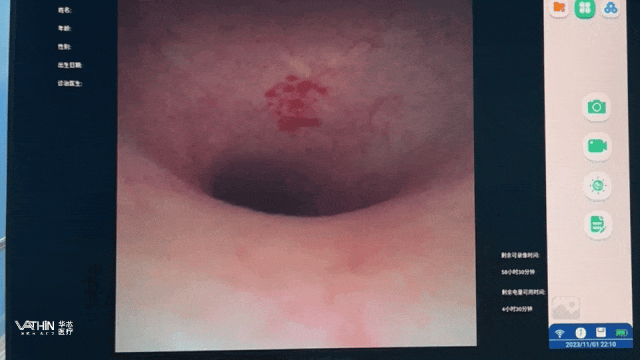

目前,泌尿领域是一次性内镜最成熟的医疗器械创新网,创新成果也最为集中。以华芯医疗一次性电子输尿管软镜为例,华芯一次性电子输尿管肾镜导管具有多种规格(6.3Fr,7.5Fr,8.4Fr), 结合华芯一次性使用输尿管导引鞘,真正实现了边碎石,边排石的效果,为碎石诊疗提供更全面的一站式解决方案。

这种设计,使得其内镜弯曲角度更大,有助于提升操作灵活度。华芯医疗一次性电子输尿管肾镜导管的弯曲角度达:向上≥285°向下≥285°,可以抵达上中下肾盏;一次性电子膀胱肾盂镜导管弯曲角度达(U/D210°),实现整个膀胱无盲区检查,清晰反观尿道内口及膀胱颈部,还可以进入膀胱憩室内,发现憩室内病变。对于前列腺增生凸入膀胱明显的患者,能够反观前列腺突入度,为手术提供术前规划。

在画质清晰度上,华芯一次性电子膀胱肾盂镜导管采用百万级高清像素。同时采用负压吸引接口设计,遇到膀胱出血、膀胱内大量絮状物漂浮、膀胱内充满灌洗液影响操作时,可随时利用负压吸引功能处理,只需按动吸引按钮,即可明显改善视野清晰度,减轻患者不适。